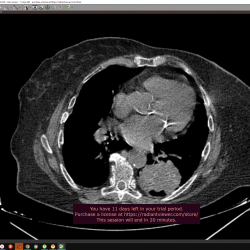

Добрый день. я новичок в кт. Помогите разобраться. В анамнезе: Рак сигмовидной кишки, опер лечение в 2015г. п\о грыжа в области стомы